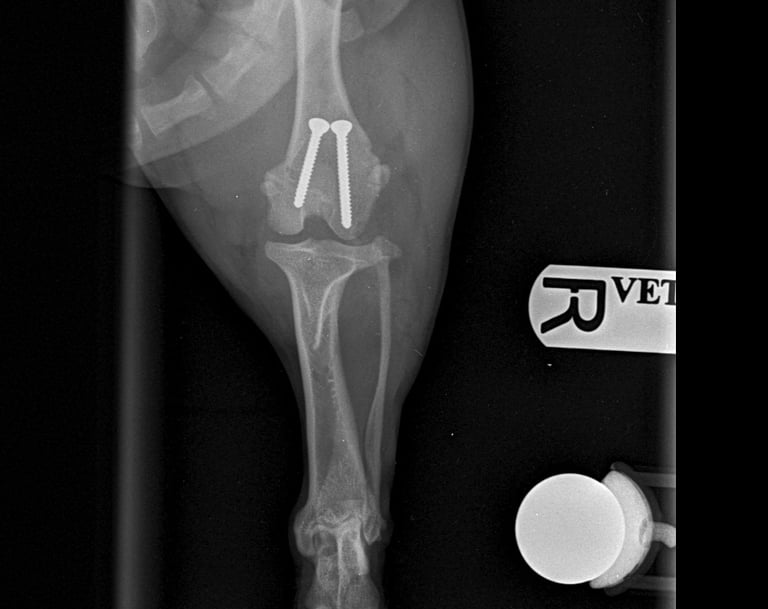

Orthopaedic surgery

Complete Surgical Equipment Package: All necessary orthopaedic equipment, power tools, and implants are brought to your clinic.

Follow-up Care: Aftercare service, ongoing management, and follow-up X-rays assessment as necessary.

The following images and case studies are intended for veterinary professionals and may include explicit surgical content, such as blood, anatomical structures, and medical procedures. These materials could be distressing to some viewers.

By clicking on the following images, you will be redirected to a new page with detailed clinical cases. Viewer discretion is advised!